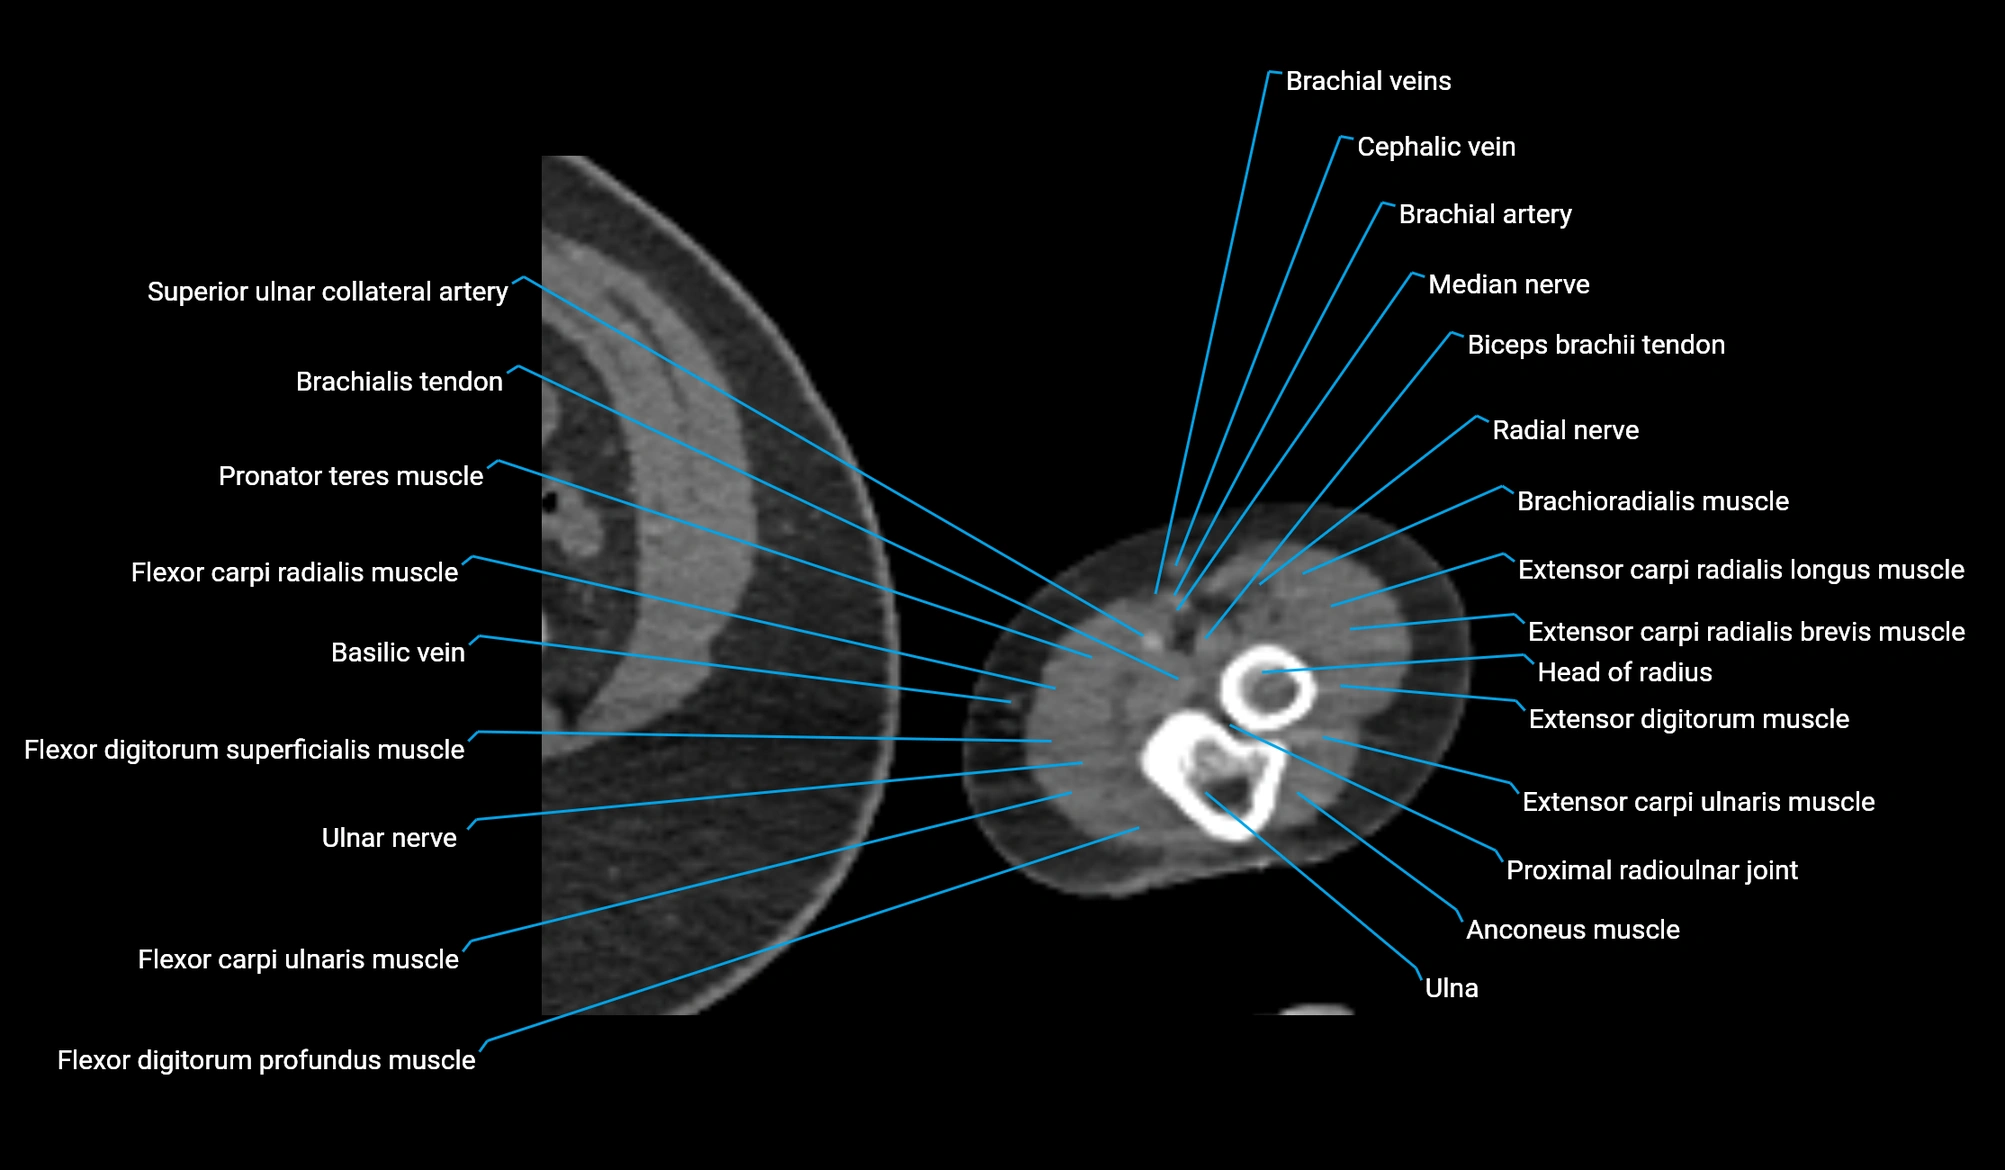

- Anconeus muscle

- Basilic vein

- Brachial artery

- Brachioradialis muscle

- Cephalic vein

- Extensor carpi radialis brevis muscle

- Extensor carpi radialis longus muscle

- Extensor carpi ulnaris muscle

- Extensor digitorum muscle

- Flexor carpi radialis muscle

- Flexor carpi ulnaris muscle

- Flexor digitorum profundus muscle

- Flexor digitorum superficialis muscle

- Head of radius

- Median nerve

- Proximal radioulnar joint

- Radial nerve

- Superior ulnar collateral artery

- Ulnar nerve